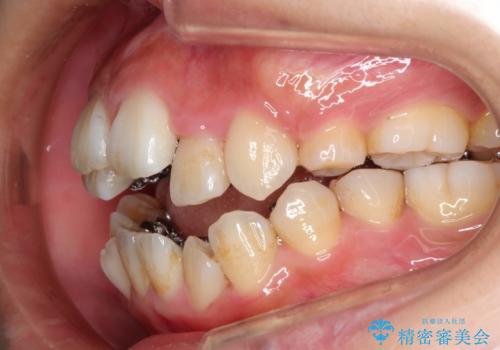

- 20代女性

- 矯正装置

- リンガル装置

- 治療期間

- 4年

- 治療回数

- 30回以上